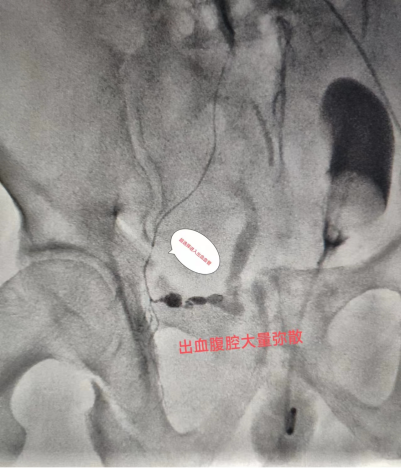

在認(rèn)真尋找出血血管

只見(jiàn)張濤主任

憑借高超技藝與熟練操作

很快便找到責(zé)任血管

精準(zhǔn)超選到出血?jiǎng)用}

給予彈簧圈

及明膠海綿栓塞治療

(圖:術(shù)中可見(jiàn)動(dòng)脈破裂出血,超選入出血?jiǎng)用}造影證實(shí))